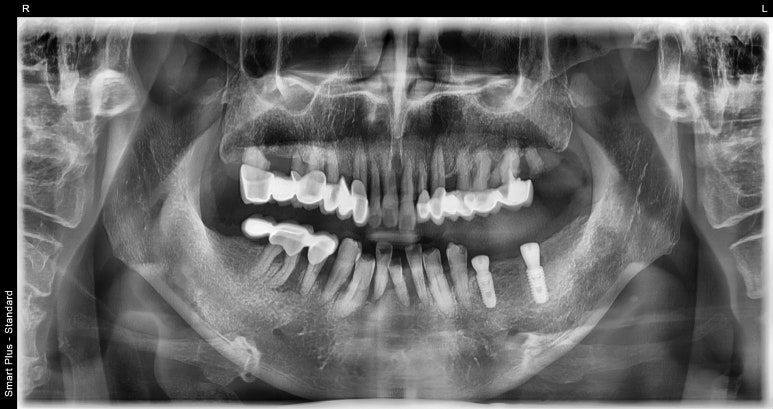

환자분의 첫 내원 시 엑스레이 사진과 입 안 사진을 함께 보여드리겠습니다.

임플란트 수술 전

2022-08-23

보시다시피 왼쪽 아래 어금니 3개를 상실한 상태에서 저희 치과로 내원해주셨는데요.